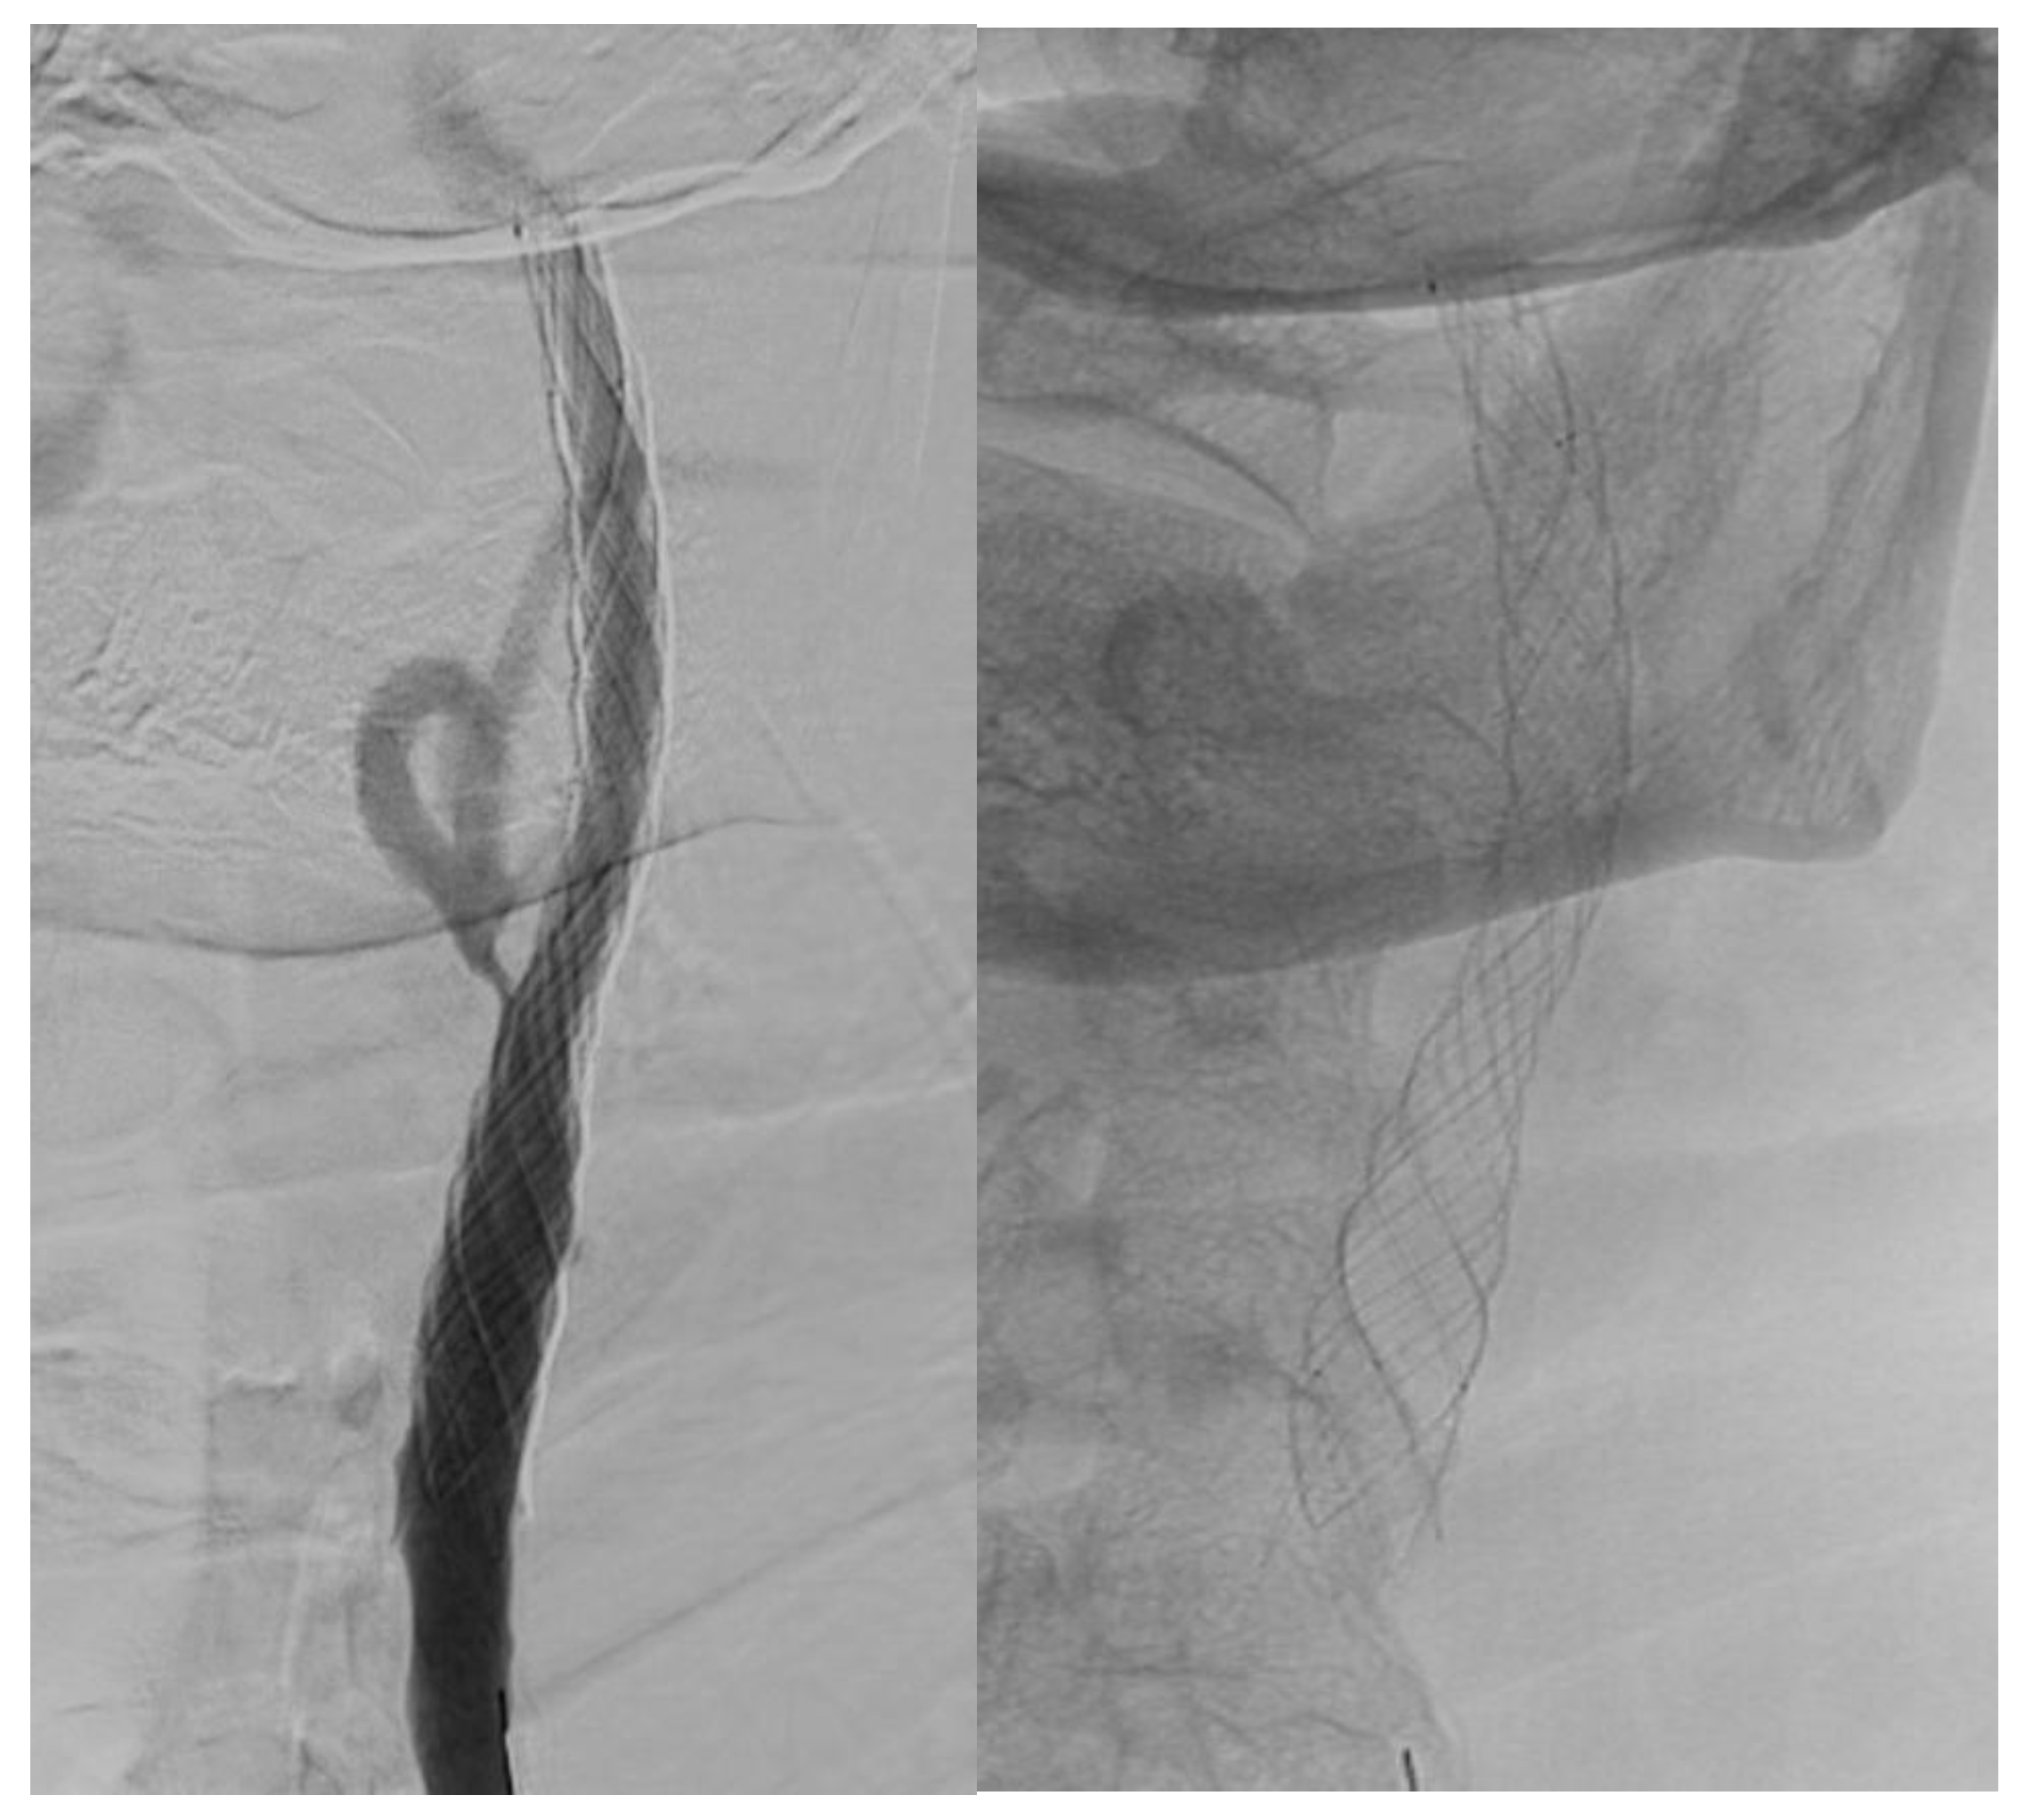

The mean stenosis grade in stented internal carotid arteries and the stenosis grade of contralateral side ICA and common carotid as well as vertebral arteries are shown in Figure 1.

Figure 4. Stenosis grade in carotid and vertebral arteries. Internal carotid artery: ICA, common carotid artery: CCA, vertebral artery: VA.

Jcm 14 00888 g004